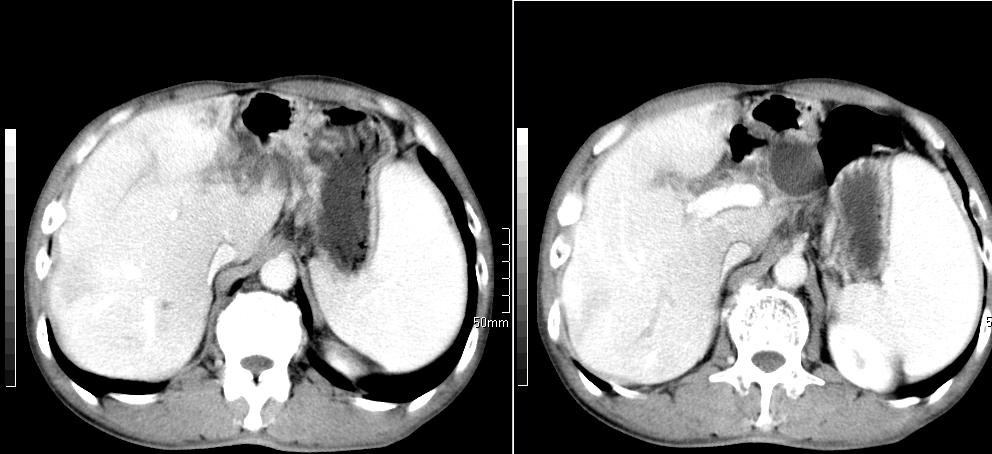

标题: CT26769:男,58岁,腹胀、腹部不适一年余 [打印本页]

标题: CT26769:男,58岁,腹胀、腹部不适一年余

肝右叶后段见小片状略低密度影,边缘不清,轻度强化,内见小血管影通过同,延迟期为等密度,考虑局灶性脂肪浸润。需与血管瘤鉴别。另有胆囊炎、脾大。

1)考虑慢性胰腺炎并假性囊肿形成。2) 慢性胆囊炎。3)肝内胆管扩张。

1肝内胆管扩张,性质待定,2慢性胰腺炎胰管扩张,胰腺颈部假囊肿,3肝左叶低密度为小囊肿,4胆囊炎。

1)考虑慢性胰腺炎并假性囊肿形成。2)肝内胆管稍扩张。